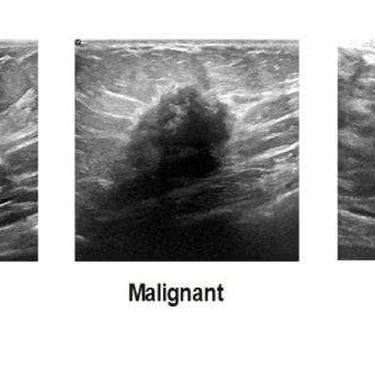

Meme Ultrasonografisi (USG):

Dens memelerde (Genç hastalar) mamografinin kör noktalarını aydınlatır.

Solid vs Kistik ayrımı: Kist ise LR 0 (Benign), Solid ve damarlanma artışı varsa LR (+) 10.0.